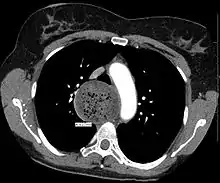

- An axial CT image showing marked dilatation of the esophagus in a person with achalasia.